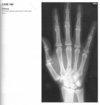

Anteroposterior view of the hands of a

patient with chronic renal failure shows subperi-

osteal resorption along the radial aspect of the

middle phalanges of the index and middle fingers

(Fig. 2.23.1, arrows). There are vascular clips from

a graft at the radial aspect of the right wrist (arrow-

heads). A lateral view of the skull in the same patient

(Fig. 2.23.2) shows a salt-and-pepper appearance.

Secondary hyperparathyroidism (HPT)

Bone resorption along the radial aspect of

the middle phalanges of the hand (especially of the

second and third digits) is considered diagnostic of

this disorder.

Bone softening may lead to

basilar invagination, wedged vertebrae, bowing of long bones, and slipped capital femoral epiphyses.